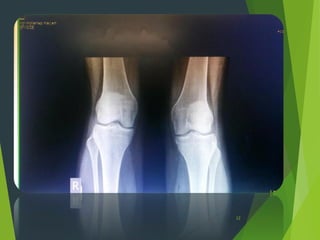

AP view

4